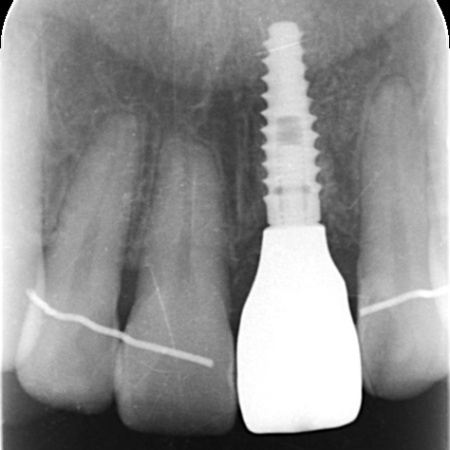

またレントゲン撮影をして詳しく検査したところ、左上前歯が細菌感染を起こしており、歯根の先端に膿が溜まっていることが判明しました。歯の土台となっている金属のメタルコアも、長期保存が不可能な状態です。

まずは左上前歯にエクストリュージョンを行い、歯と歯茎の境目を整えたうえで抜歯を行います。抜歯と同時にインプラントを埋め込み、治療中の審美性を考慮して仮歯を装着しました。